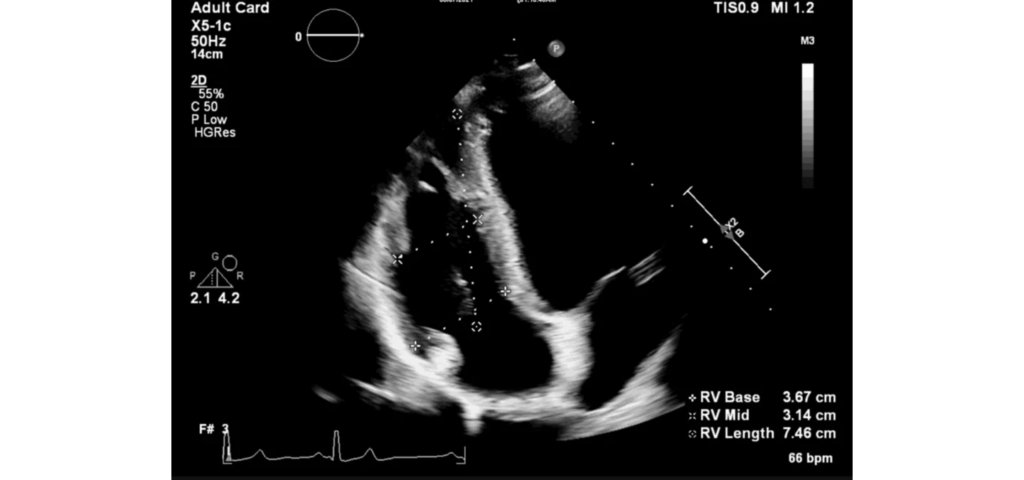

EPIQ CVx, our premium cardiovascular ultrasound system built on our innovative, modular, industry-leading ultrasound platform, has powerful AI-based capabilities and advanced diagnostic solutions to help you transcend today’s complexities and propel echocardiography into the next dimension. This enables you to achieve greater consistency, accessible innovation, smarter workflows, and easier scalability.